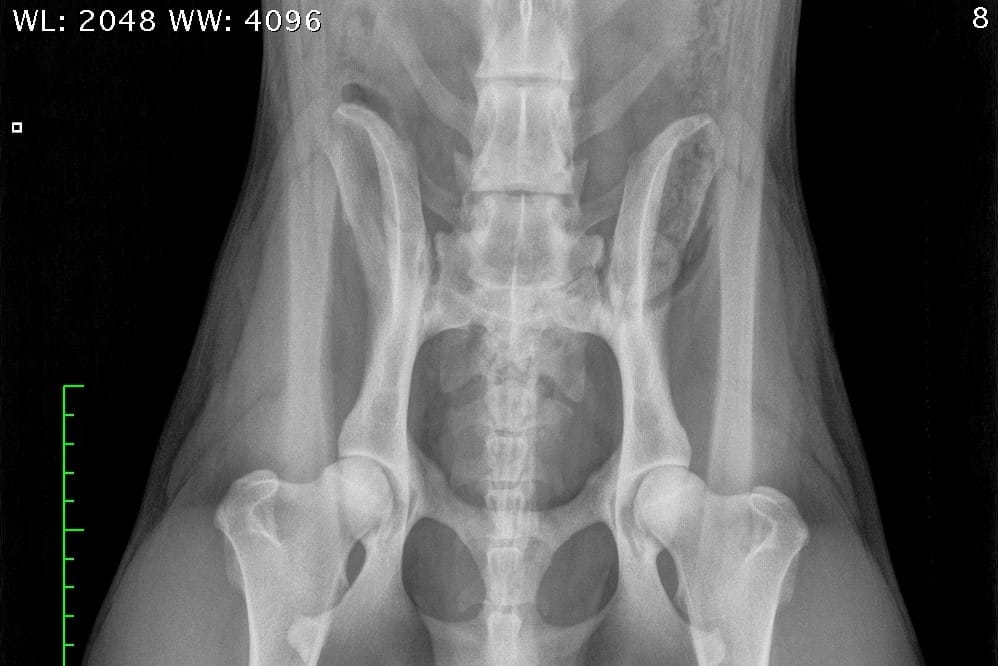

A normal canine spine consists of 7 cervical (C1-7), 13 thoracic (T1-13), 7 lumbar (L1-7) and 3 sacral vertebras (S1-3) resulting the total of 30 vertebras. Calculation starts from first thoracic vertebra (T1). The number of caudal vertebras (CD) vary.

Sacrum connects the lumbar spine to pelvis. It’s a part of the pelvis and it lies between the lumbar spine and tail. Sacrum is strong, triangular in shape and it sits between the hip bones. Normal sacrum consists of three fused vertebral segments; S1, S2 and S3.

LTV0